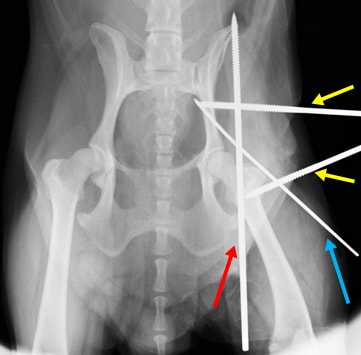

関節包再建術後、大腿骨頭の背側脱臼を防ぐためのDeVitaピンを挿入します。(赤矢印)

DeVitaピン(赤矢印)とクロスピン(青矢印)を挿入後、大腿骨の外旋を防ぎ、